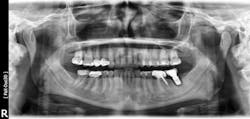

Failures and complications associated with bone augmentation can have a devastating effect on the outcome of dental implant treatment. These complications are classified as either early or late. Early complications include wound dehiscence, membrane and graft exposure, and infection, with the most common complication being wound dehiscence (figures 1a–1c). A strong correlation has been shown between flap tension and wound dehiscence, with wound breakdown occurring in 40% of cases where the flap tension reached 40.1 N as opposed to 10% for flap tensions < 0.1 N.1

Figures 1a–1c: Wound dehiscence occurring after bone augmentation procedures.